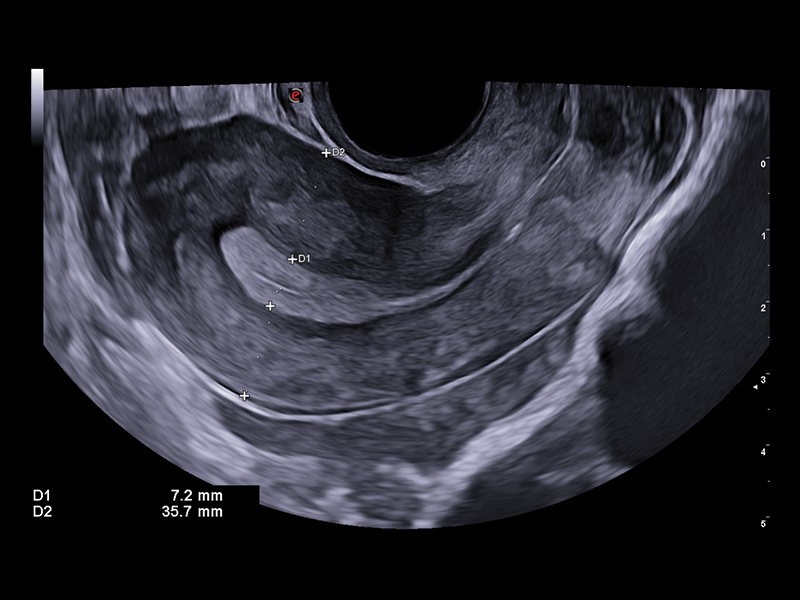

Ultrasound plays a significant role in the field of medically assisted procreation (MAP) and reproductive medicine. Follicle monitoring is one critical aspect in fertility management. XVRA is the innovative Esaote tool that automatically calculates follicle volume, thus helping in the identification of the best oocytes to be collected, to increase the chance of pregnancy.